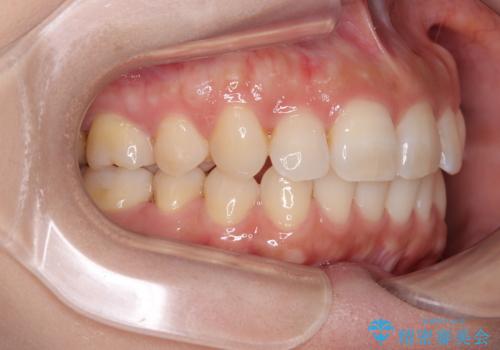

目立つ八重歯を改善 ワイヤー装置での抜歯矯正

上顎の正中位置をほぼ保った状態で、綺麗に仕上げることができました。